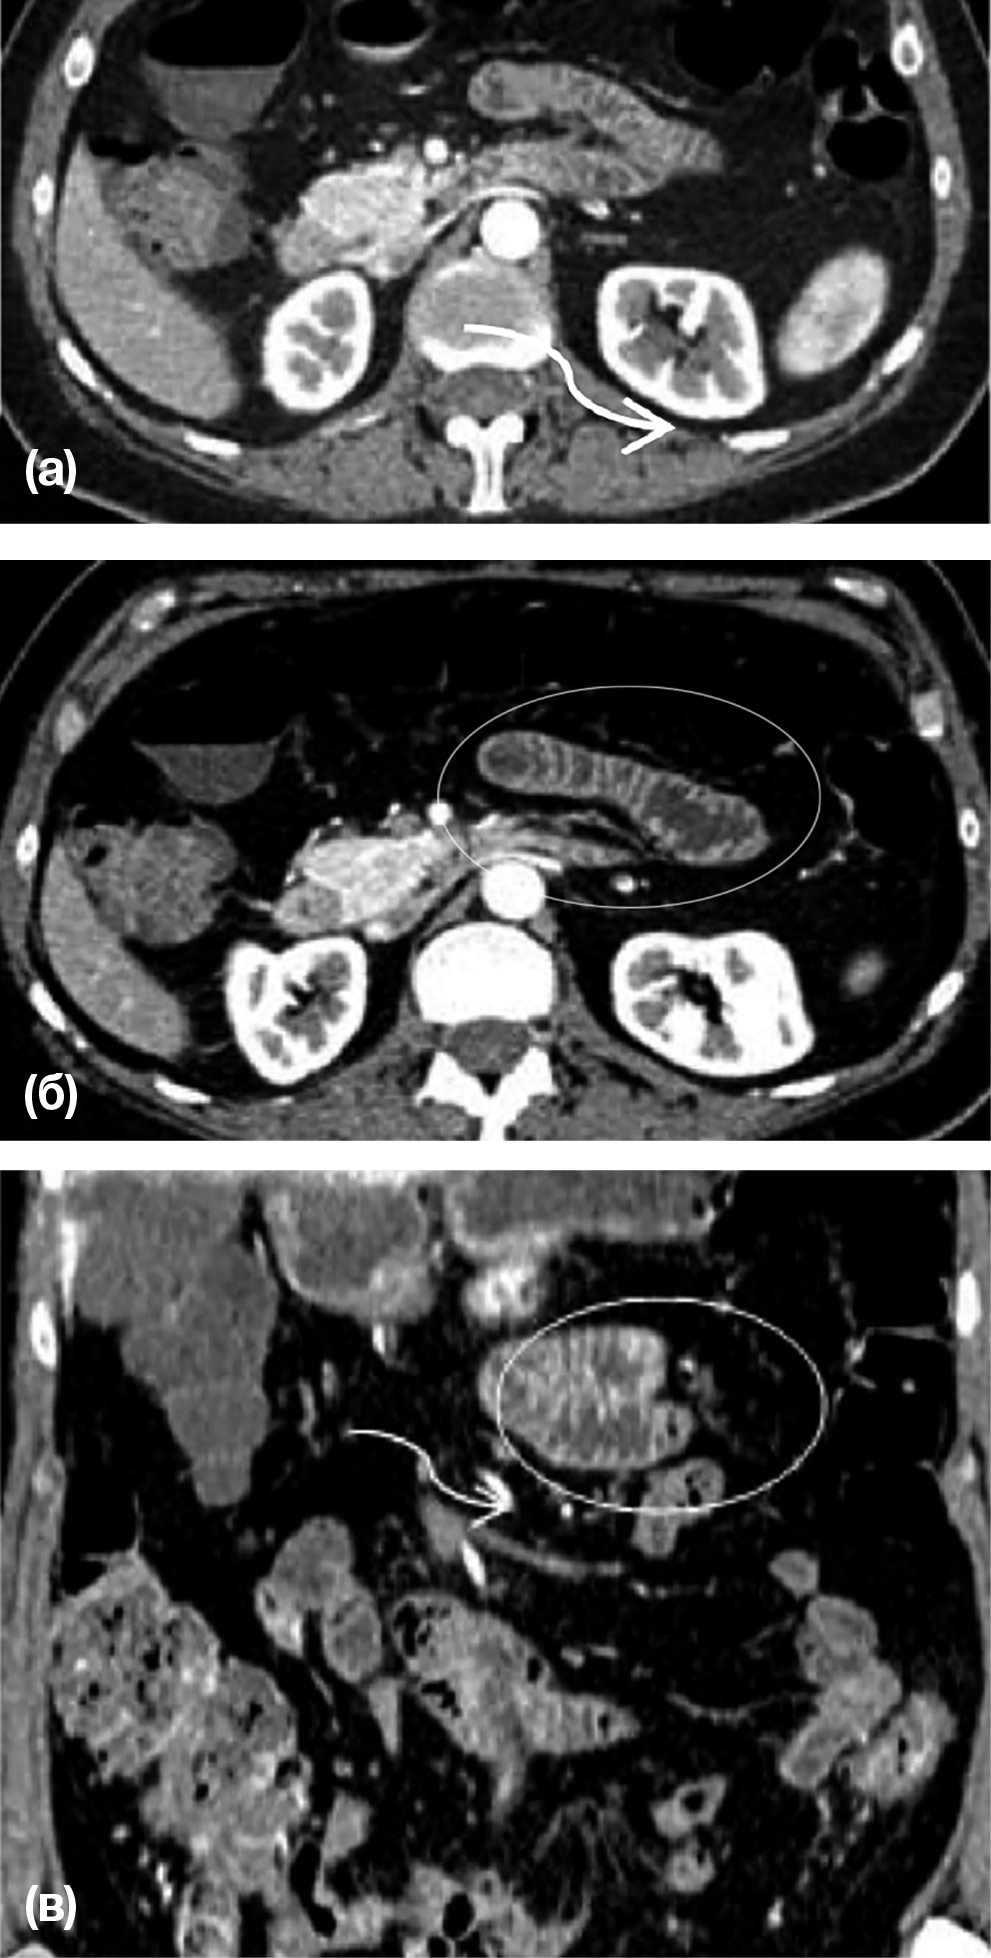

Рис. 2. Пациент Д., 61 год. Врожденная левосторонняя парадуоденальная грыжа

Примечание. Венозная фаза контрастного усиления. (а) — аксиальная КТ, (б, в) — сагиттальные КТ-реконструкции изображений. В пространстве между поджелудочной железой и желудком определяются расширенные петли тощей кишки, содержащие горизонтальный уровень «газ-жидкость» (овалы). Сосудистый рисунок прилежащей брыжейки обогащен, сосуды смещены к центру грыжи. Грыжевые ворота маркируются нижней брыжеечной веной и восходящей левой кишечной артерией (стрелка). На изображении (а) эти сосуды располагаются кпереди и медиально относительно грыжевого отверстия и внедренных петель кишечника.